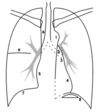

The pattern of how you will scan the mediastinum and heart of a CXR.

A